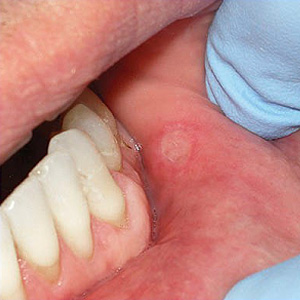

Canker sores. Known as aphthous ulcers, these round sores with a yellow-gray center and a red “halo” can break out on the inside cheeks, tongue or back of the throat. Unless they don't heal within a couple of weeks or seem to be increasing in frequency, they're nothing to worry about. They can, however, cause a burning or stinging sensation. We can reduce this discomfort and speed healing with over-the-counter ointments or prescription options like topical or injected steroids.